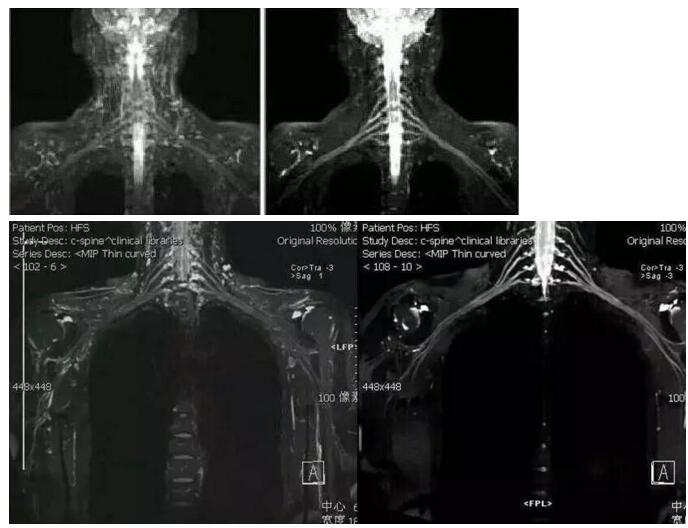

左圖為改進(jìn)前的圖像,右圖為新技術(shù)的圖像

由我院醫(yī)學(xué)影像中心經(jīng)過多次討論出來的新方案做出來的新圖像,相比之前的技術(shù),新方案的圖像幾乎沒有受到的背景信號干擾。

磁共振成像新技術(shù)做出來的圖像可清晰地顯示臂叢神經(jīng)全貌及周圍組織結(jié)構(gòu)關(guān)系,能顯示神經(jīng)根的撕裂,還能同時顯示合并存在的脊膜膨出、腦脊液外漏、脊髓出血、水腫等。

而且 磁共振水成像技術(shù)對顯示蛛網(wǎng)膜下隙及腦脊液的外漏更為清楚。在臂叢神經(jīng)病變的診斷中起有不可磨滅的作用。

根據(jù)檢查所作圖像重建的三維圖像,我們可以從各個方位觀察臂叢神經(jīng)